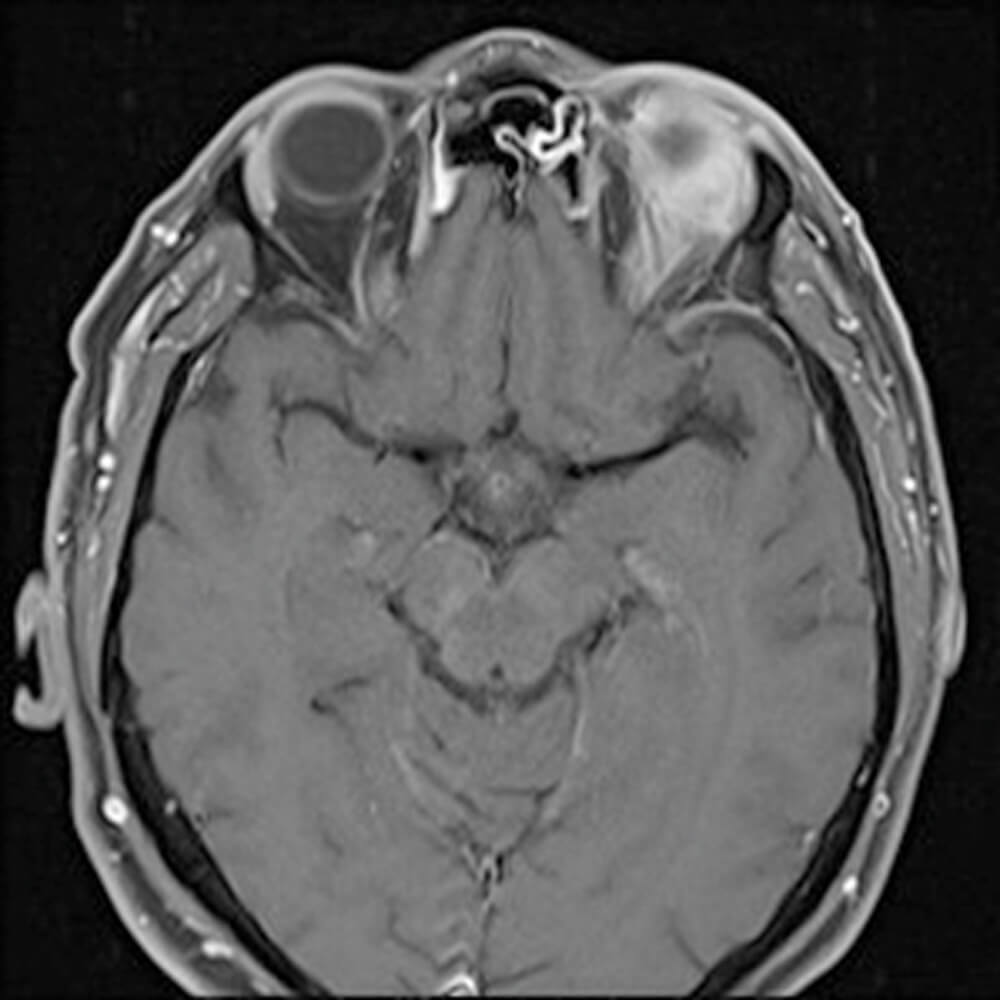

Figure 2: MRI scan of head.

This was then followed up with an MRI which demonstrated a soft tissue mass in the left superolateral orbit extending around the superior rectus complex and the left lateral rectus that was exerting mass effect over the left eye globe.